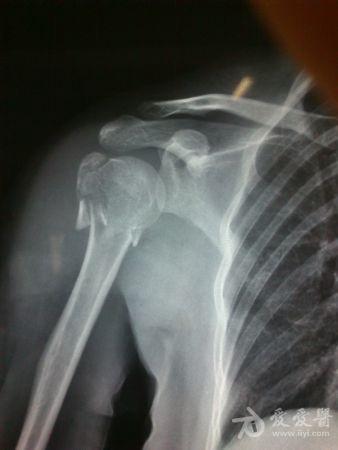

病史特点及病情摘要:1、患者女性,51岁。2、患者自诉入院前1年余因右肱骨外科颈骨折在外院行切开复位内固定术,术后右肩关节疼痛、活动受限,一直未予处理,今为明确诊治入院。患者精神、食欲、睡眠尚可。3、既往史、个人史、家族史无特殊。4、入院查体:生命征平稳,心肺腹检查未见异常,NS(-)。专科情况:右上臂近端内侧见一约15cm手术切口疤痕,愈合佳,右肩关节能外展20度,前屈、后伸及旋前、旋后功能障碍,余关节活动好。舌质红,苔薄白,脉实。5、辅助检查:右肩关节正侧位片:右肱骨外科颈骨折内固定术后再骨折伴右肩关节脱位。

诊断:右肱骨外科颈骨折内固定术后再骨折伴右肩关节脱位

我院门诊

同意楼主观点,患者第一次手术复位欠佳,但可勉强接受。但钉子穿出,是手术后肩关节疼痛的主要原因,现在看骨折已愈合,头无明显头坏死迹象,只需取出内固定,麻醉下活动肩关节,使肩关节活动度改善,术后加强功能锻炼,应该恢复不错。